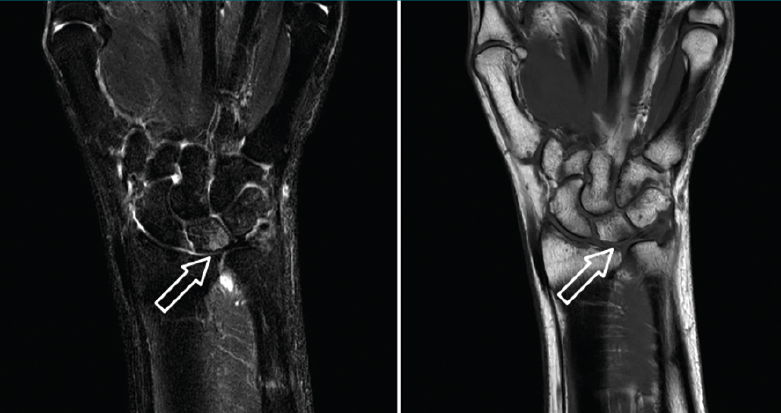

Dentro de las pruebas de imagen a realizar, son obligatorias la proyección posteroanterior (PA) de muñeca en posición neutra y una proyección PA en pronación y con el puño cerrado para poder evaluar una posible varianza positiva dinámica. Las radiografías pueden mostrar una esclerosis o quistes subcondrales en la cabeza del cúbito, el extremo proximal cubital del semilunar o el extremo proximal radial del piramidal(9). En casos severos, pueden observarse osteofitos a nivel de la articulación cubitocarpiana. De nuevo, es importante evaluar la presencia de signos artrósicos al nivel de la ARCD y la morfología de la articulación en el plano coronal, puesto que pueden condicionar la elección de la mejor opción quirúrgica. En la radiografía lateral se debe evaluar si existe subluxación de la ARCD con prominencia dorsal de la cabeza del cúbito. Es de gran ayuda y muy recomendable realizar radiografías de ambas muñecas para comparar las imágenes con la muñeca contralateral. Estrictamente hablando, no sería siempre necesario solicitar otras pruebas de imagen como la resonancia magnética (RM) para poder diagnosticar este síndrome, pero es cierto que esta puede dar detalles minuciosos sobre cuáles son las estructuras lesionadas y, además, es útil para detectar otras posibles patologías ocultas(9). En las fases iniciales, el cartílago articular afectado puede presentar signos de fibrilación y condromalacia. También se puede detectar hiperemia o edema en las zonas afectadas (Figura 3), esclerosis subcondral o cambios quísticos. La RM –y, más específicamente, la artro-RM– es especialmente útil para valorar la integridad del CFCT, del ligamento LT y para valorar otras posibles causas de dolor cubital de la muñeca cuando hay dudas sobre el diagnóstico.

Figura 3. Imagen de resonancia magnética que muestra edema en el hueso semilunar secundario a impactación cubital.